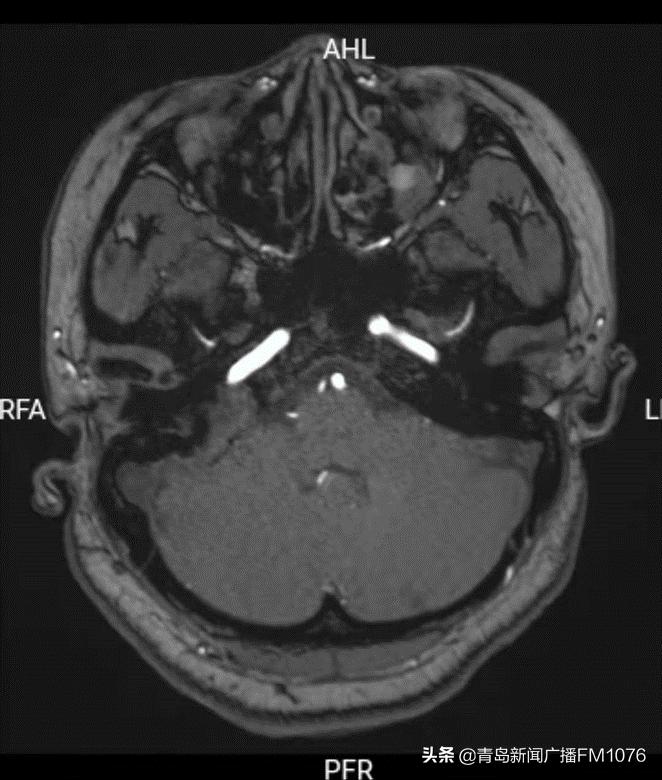

患者的病变位于右侧颈静脉孔区-颞骨岩尖部-后颅窝部,有一块很大的不规则软组织影,周围骨质已经出现破坏,病变周围密布着颈内动脉、乙状窦、颈内静脉、面神经。李主任非常清楚,这是一颗十分“狡猾”的肿瘤,不仅位置深在,而且它周围布满神经血管,稍有不慎,便会给患者造成更大的伤害。患者已出现面部抽搐,表明肿瘤已经刺激到面神经,如不尽快手术,肿瘤会不断增长,患者将会出现面瘫、颅内感染等更严重症状。

肿瘤周围相关的神经血管结构示意图